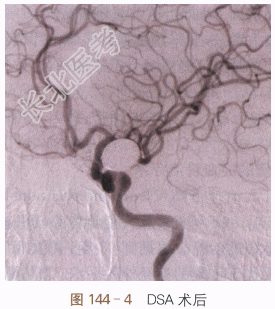

经血管动脉瘤腔弹簧圈填塞术:①术前DSA如图144-1所示;②DSA路图示微导管到位(见图144-2);③DSA路图示动脉瘤腔内盘曲的弹簧圈(见图144-3);④术后DSA(见图144-4)。

CT扫描显示蛛网膜下腔出血,MRA和DSA显示左侧后交通起始部动脉瘤,符合动脉瘤破裂导致蛛网膜下腔出血。逐行全麻下右侧股动脉穿刺插管,选择性插管入左右颈内动脉和椎动脉造影,测量动脉瘤0.8×0.9cm²大小,并评估脑内血流动力学情况。取动脉瘤和载瘤动脉关系显示最佳位置。①在肝素化后,置导引导管入患侧颈内动脉C₂段,然后在微导丝导引下置放导管头入动脉瘤腔并撤除微导丝。②再从大到小逐一置入不等大小弹簧圈共11枚(15×500mm,14×340mm×2,13×430mm,13×320mm,10×250mm,3×80mm,2×60mm,1×20mm,1×10mm)。③术后造影显示动脉瘤完全致密闭塞,载瘤动脉通畅。④逐拔管,股动脉缝合止血。复苏后返病房。采用抗血管痉挛治疗2周,腰穿放血性脑脊液2次。